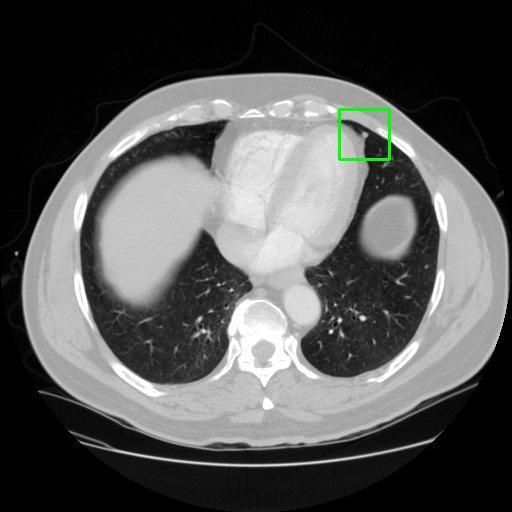

We developed an AI-based system using deep learning models for analyzing lung CT scans to detect and classify pulmonary nodules. We chose the YOLOv11 architecture for its enhanced object detection capability and adapted it specifically for medical imaging, incorporating pixel-level precision and severity classification.

Classification into three severity levels with colored bounding boxes.

Designed a severity classification system that categorizes nodules into null, moderate, and severe using colored bounding boxes, assisting in rapid clinical decision-making.